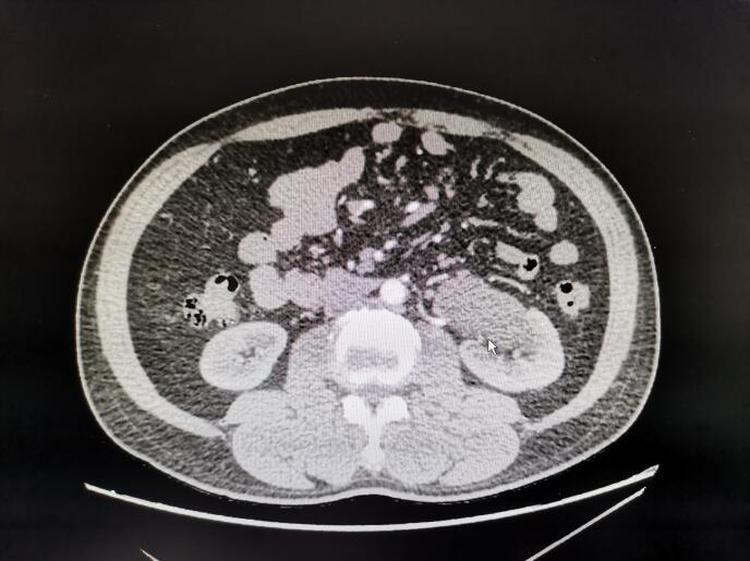

一例31岁男性患者,因“右侧腰背区疼痛1天”,行CT考虑为腔静脉后异位输尿管致肾积水,完善术前准备后为其行了"经腹腹腔镜下腔静脉后输尿管成形术",手术顺利,患者已出院。

一例为47岁男性患者,因“体检发现左肾积水”入院,行CT考虑左肾异位动脉后输尿管致肾积水,完善术前准备后为其行了"腹腔镜下异位肾动脉后输尿管成形术",手术顺利,已出院。